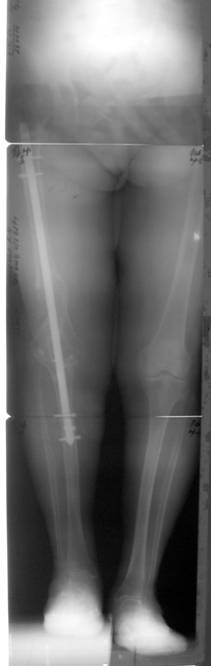

ВИЧ. Поэтому в подобном случаем мы бы "пошли" на артродез с

использованием блокируемого гвоздя с антибактериальным покрытием. Если

при остром укорочении ушить рану ввиду гофрирования мягких тканей не

удастся, наложите аппарат поверх гвоздя (только проксимальное

блокирование!), после заживления раны дозированно устраните диастаз и

заблокируйте гвоздь дистально.

Имя     : Артродез.jpg